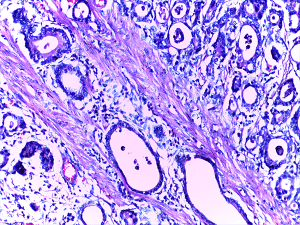

A micrograph of stomach cancer where the glands are seen infiltrating the muscle layer.

Image via the Department of Pathology, Calicut Medical College